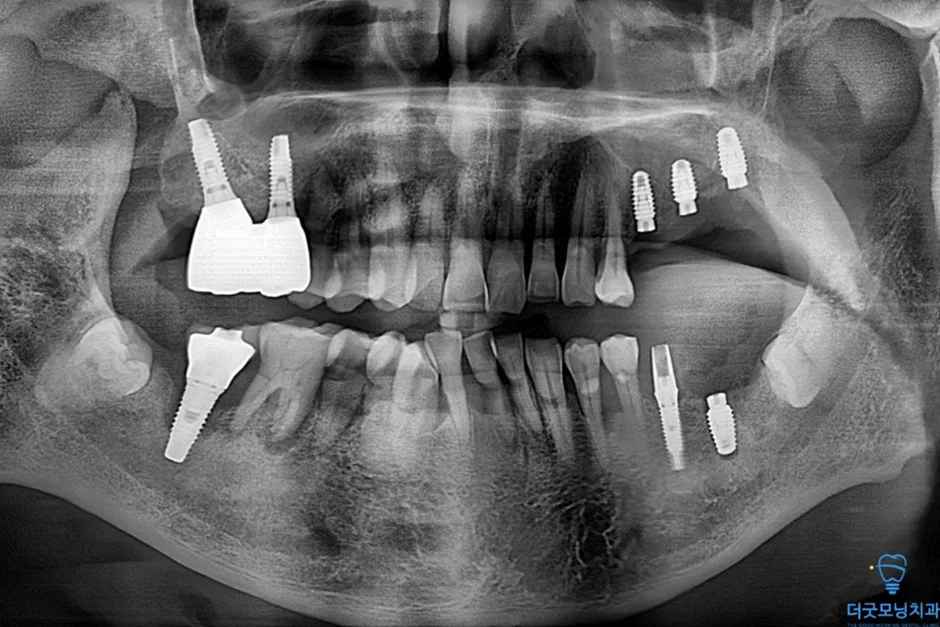

먼저 파노라마 엑스레이와 CT를 통해 구강 전체 상태를 확인하였습니다.

■ 왼쪽 위 (상악 좌측)

상악동이 많이 함기화되어 있어 상악동 골이식(치조정 접근 상악동 거상술)이 반드시 필요한 상태였습니다. CT 확인 결과 가용골이 매우 부족한 것이 명확히 확인되었습니다.

■ 오른쪽 위 (상악 우측)

치주염으로 인해 치아가 흔들리는 상태였으며, 발치 후 즉시 임플란트 식립을 계획하였습니다.

■ 아래 양쪽 (하악 좌·우측)

임플란트 주위염이 발생하여 기존 임플란트를 제거하고 재수술이 필요한 상태였습니다. CT 상 신경관까지 어느 정도 거리가 확보되어 재수술은 무리 없이 진행 가능하였습니다.